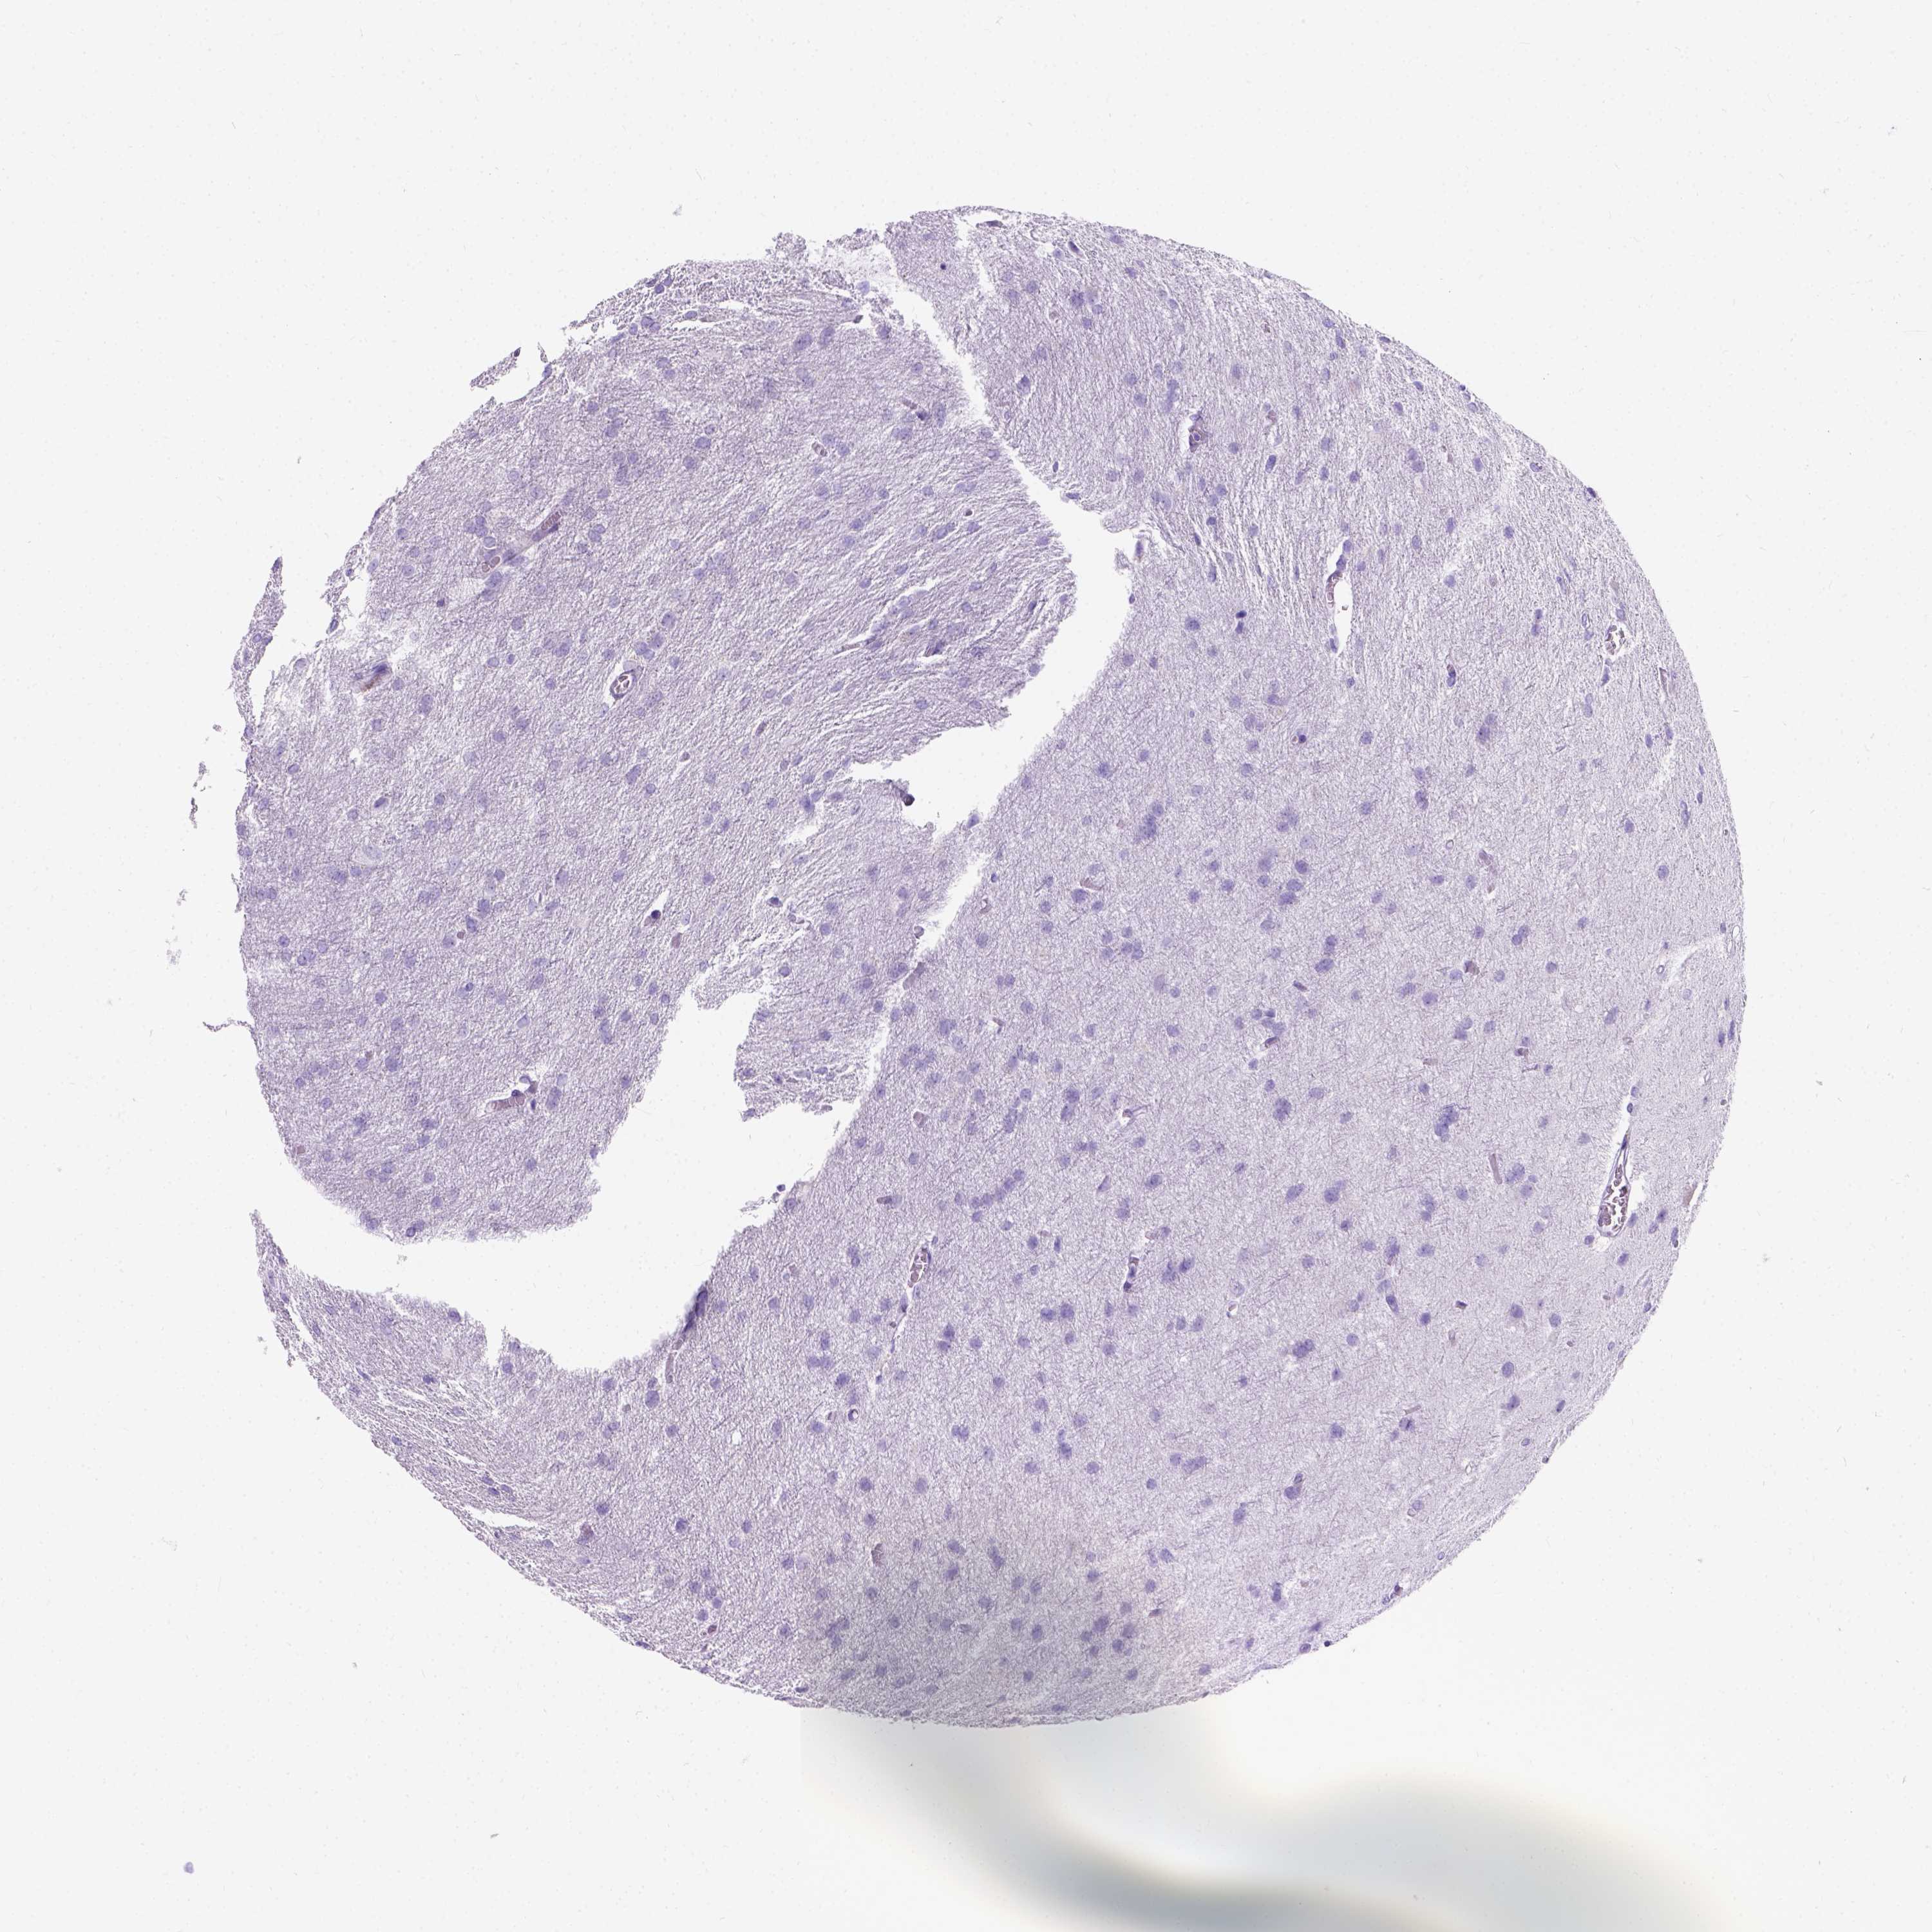

GLIOMA - Protein expressioni

A mouse-over function shows sample information and annotation data. Click on an image to view it in a full screen mode. Samples can be filtered based on level of antibody staining by selecting one or several of the following categories: high, medium, low and not detected. The assay and annotation is described here.

Note that samples used for immunohistochemistry by the Human Protein Atlas do not correspond to samples in the TCGA dataset.

Antibody stainingi

Antibody staining in the annotated cell types in the current human tissue is reported as not detected, low, medium, or high, based on conventional immunohistochemistry profiling in selected tissues. This score is based on the combination of the staining intensity and fraction of stained cells.

Each image is clickable and will lead to virtual microscopy that enables deeper exploration of all samples and also displays staining intensity scores, fraction scores and subcellular localization as well as patient and tissue information for each sample.

Antibody HPA021286

Staining

High

Medium

Low

Not detected

Intensity

Strong

Moderate

Weak

Negative

Quantity

>75%

75%-25%

<25%

None

Location

Nuclear

Cytoplasmic/membranous

Cytoplasmic/membranous,nuclear

Glioma, malignant, Low grade

Glioma, malignant, High grade